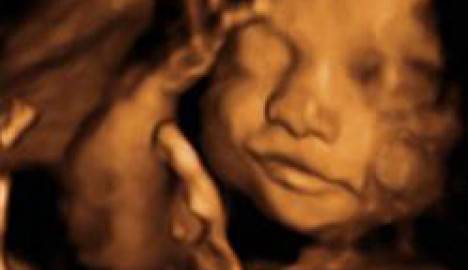

Fanno le facce. Osservando ecografie fatte in 4D i medici della Durham University hanno visto che dalla ventiquattresima settimana i bambini possono assumere due espressioni facciali simili a un sorriso. Dalla trentaseiesima invece possono esprimere facce più complesse come ciglia corrucciate, naso arricciato e bocca tesa.